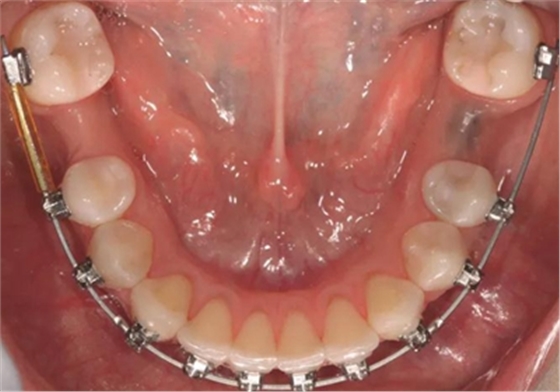

圖1b.臨床檢查顯示牙槽嵴萎縮,右下第一磨牙的無(wú)牙間隙近遠(yuǎn)中距離為6.5mm,左下第一磨牙為9mm

為患者采用了直絲弓自鎖托槽(Damon,Ormco)。最開(kāi)始用0.016×0.025 英寸的不銹鋼弓絲(Damon,Ormco)進(jìn)行矯正和排齊,歷時(shí)7 個(gè)月。在磨牙直立加力之前,下頜第一磨牙位點(diǎn)無(wú)牙區(qū)的近遠(yuǎn)中距離為右側(cè)6.5mm、左側(cè)9mm(圖1)。磨牙遠(yuǎn)移和直立的目標(biāo)是實(shí)現(xiàn)雙側(cè)最終冠修復(fù)體的近遠(yuǎn)中直徑達(dá)到10mm。右側(cè)第一磨牙位點(diǎn)的大小差異比左側(cè)更大,牙槽嵴吸收更多,頰舌徑約4.5mm(圖2)。在詳細(xì)解釋同期牙槽嵴增量和加速磨牙直立程序后,患者選擇右側(cè)位點(diǎn)進(jìn)行種植治療。因此,為了加速該位點(diǎn)的空間建立,圍繞第二磨牙行選擇性去皮質(zhì)術(shù)和同期牙槽嵴增量術(shù)。

經(jīng)過(guò)最初1年的正畸排齊后,右側(cè)下頜第一磨牙無(wú)牙區(qū)的近遠(yuǎn)中距離由6mm增至7mm,左側(cè)下頜第一磨牙的近遠(yuǎn)中距離由7mm增至8mm(圖4)。取得患者知情同意后,采用與病例1中描述的相同技術(shù)和材料進(jìn)行同期牙槽嵴增量和加速磨牙直立程序(圖5a-5g)。除了右側(cè)磨牙后區(qū),在右側(cè)第二和第三磨牙根部之間也進(jìn)行了去皮質(zhì)術(shù)(圖5d)。骨增量術(shù)后,即刻將0.016×0.022 英寸帶有30° 后傾彎的鈦鉬合金絲(Dentsply)置于兩側(cè)。6周后,以半個(gè)托槽的距離進(jìn)行主弓絲套推簧雙側(cè)輕加力(圖5h)。